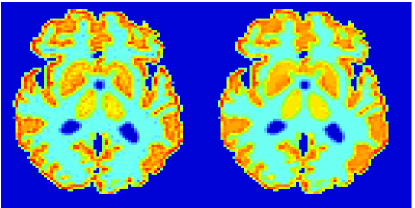

In the images shown in the figures we illustrate the calculated uptake rates of the FDG. Images for the CMRGlc can be obtained by directly scaling . In figure 1 we compare the result of using Patlak and TV-Patlak for estimating the uptake rates with respect to no noise, noise in the input function, Poisson noise in the sinogram, and finally with respect to the case in which the irreversibility assumption is violated but without noise in the sinogram or input data. In each case the histogram of the relative errors is given on the left, the Patlak image in the middle and the TV-Patlak on the right. The different scales in the histograms are due to the total number of results illustrated. When there is no noise (triples and ) the histogram illustrates results over all voxels but only one simulation, while for the noisy simulations the results are for all voxels over all realizations of the noise. The TV-Patlak images are more homogeneous in all cases and the relative errors are smaller. The figures clearly show the improvements of employing the TV-Patlak method as compared to using Patlak independently for each voxel. This is confirmed in figure 2 in which images with noise in the sinogram, positive and different noise levels in the input function are shown.